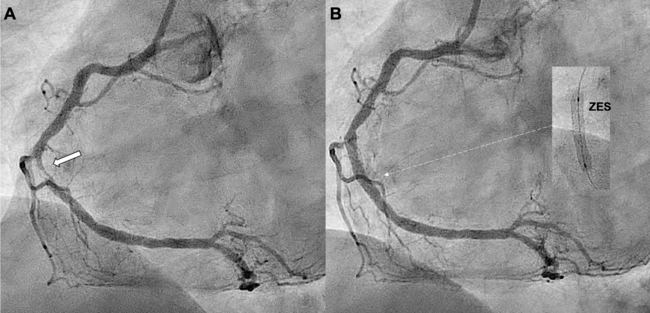

Two hours later, the patient developed recurrent chest pain with inferior ST-segment re-elevation. Repeat CAG revealed acute stent thrombosis (AST) (Figure 2A, Video 2). Thrombus aspiration was performed, and intravascular ultrasound (IVUS) showed a large diffuse intramural hematoma (IH) distal to the ZES, without underexpansion or malapposition (Figure 2B). The IH was fenestrated using a 3.5 x 6.0-mm cutting balloon (Figure 3A, Video 3). Repeat IVUS confirmed multiple fenestration tracts (Figure 3B, Video 4). Two additional overlapping ZES were successfully implanted (Figure 3C). The patient was discharged uneventfully after 48 hours and remained asymptomatic at the 1-month follow-up.